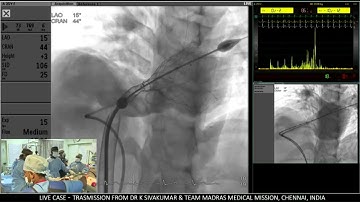

Venus P-valve loading | Step by step guide